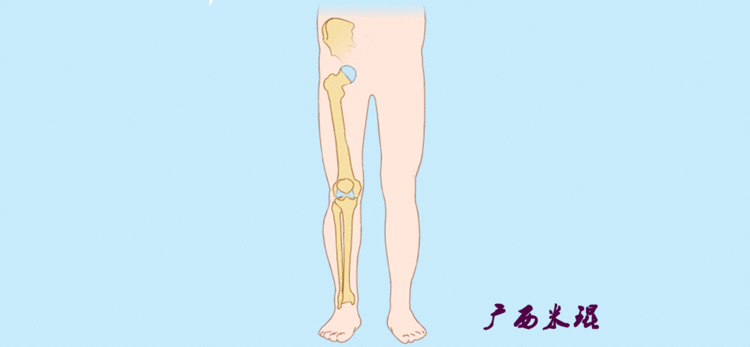

开始接触时可能我们对这些轴有点混乱,通过下面的这张图片就能清楚的了解下肢几个轴之间的关系。

最常见的下肢畸形发生于冠状面,即膝内外翻畸形,冠状面的对线异常通过应用“对线异常检验”进行分析,机械轴的偏移(MAD)表现为对线异常。

膝内翻是指下肢力线通过膝关节中心点内侧,距中点2mm以上,偏内超过15mm为显著膝内翻。膝外翻是指下肢力线通过膝关节中心点外侧,距中点2mm以上,偏外超过10mm为显著膝外翻。